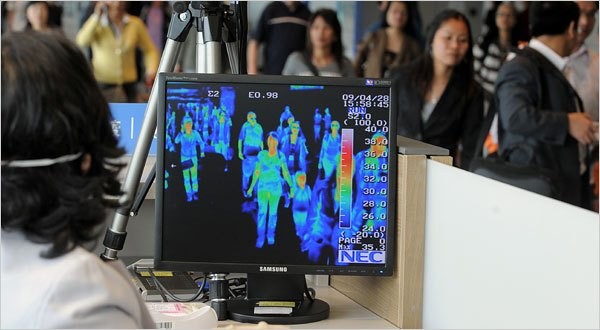

Đặc biệt tổ chức giám sát chặt chẽ bằng máy đo thân nhiệt từ xa và quan sát tình trạng sức khỏe tất cả các hành khách nhập cảnh có về từ thành phố Vũ Hán, tỉnh Hồ Bắc, Trung Quốc; phát hiện sớm, cách ly và xử lý kịp thời các trường hợp nghi ngờ mắc bệnh truyền nhiễm, có báo cáo kịp thời cho các cơ quan quản lý để phối hợp chỉ đạo giải quyết.

Theo thông tin từ Cơ quan đầu mối thực hiện Điều lệ Y tế quốc tế và hệ thống giám sát dịch bệnh Việt Nam, hiện nay Trung Quốc tiếp tục ghi nhận thêm các trường hợp viêm phổi cấp chưa rõ nguyên nhân tại thành phố Vũ Hán, tỉnh Hồ Bắc. Tính đến ngày 06/01/2020, đã ghi nhận 59 trường hợp mắc, chưa ghi nhận trường hợp tử vong. Ảnh minh họa: Internet